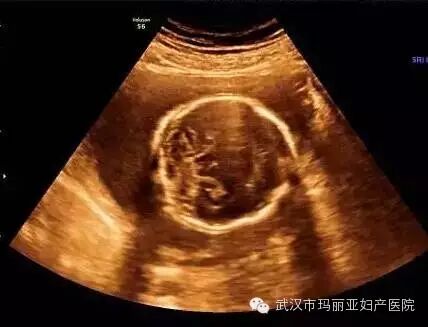

武汉玛丽亚妇产医院引进的世界领先的美国GE-E8四维彩超设备室目前世界上最先进、分辨率最高的彩色超声设备,具有即时立体成像、清晰准确的特点。

它能够多方位、多角度地观察宫内胎儿的生长发育情况,为早期诊断胎儿先天性体表畸形和发育异常提供科学依据。还能对胎儿的体表进行检查,如唇裂、脊柱裂、大脑、肾、 骨骼发育不良等,以便尽早的进行治疗。

玛丽亚美国GE-E8四维彩超排畸成功案例